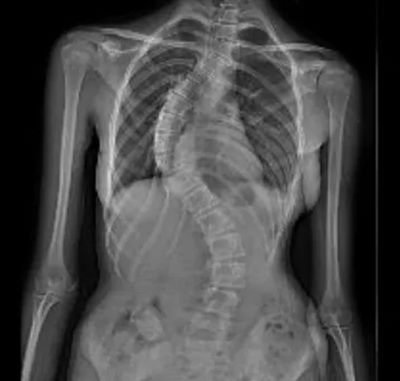

▲ 术前X线

影像学显示,小范胸椎侧弯达58°,伴有明显椎体旋转与胸廓变形。肺功能提示呼吸已受影响。闫鹏主任解释道:“Cobb角超过45°–50°且骨骼未成熟时,侧弯很可能会继续加重。小范正处于生长高峰,侧弯角度大、进展快,支具已无法控制,手术是当前唯一有效的治疗方法。”